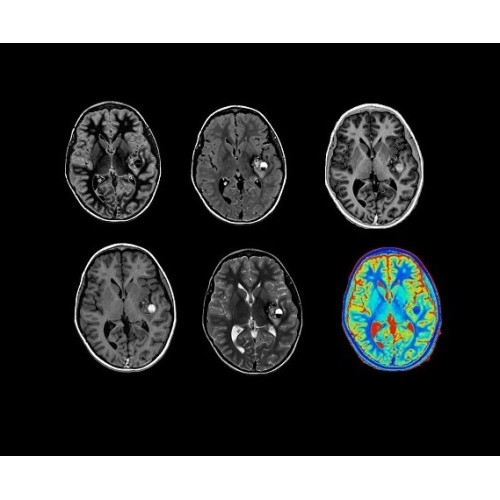

В системе SIGNA PET/MR есть все инструменты, необходимые для выявления маркеров разных заболеваний и для создания новых протоколов. ПЭТ/МРТ можно использовать совместно с мультиядерной спектроскопией в лаборатории in vivo для изучения быстрых биохимических процессов. Кроме того, PET ToolBox и набор инструментов Orchestra предоставляют персональный доступ к функциям реконструкции изображений для ПЭТ и МРТ, ускоряя и упрощая работу с необработанными данными.

• Специальный пакет приложений для измерения и сравнения объемных изображений ЦНС с нормами поможет вам в диагностике нейродегенеративных заболеваний, а дополнительные инструменты визуализации — в постановке точного диагноза с помощью бета-амилоидов и радиоизотопных маркеров ФДГ.

• In vivo лаборатория — получайте полные данные биохимических процессов in vivo с мультиядерной спектроскопией на SIGNA PET/MR.